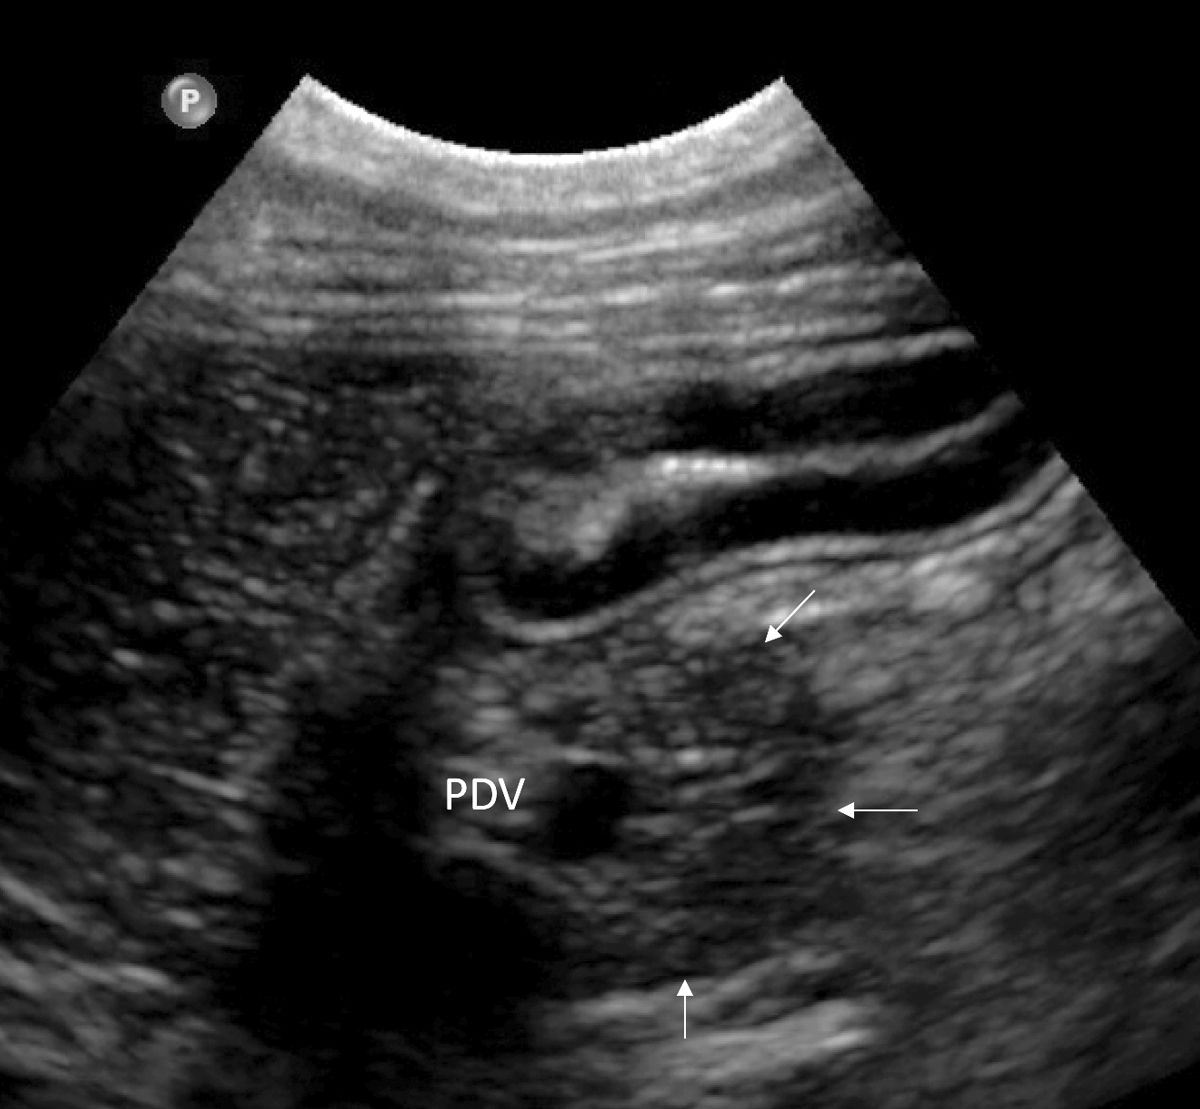

L'ecografia è utile per l'imaging del pancreas, sebbene la valutazione in modo accurato richieda una certa esperienza. Il pancreas normale è discretamente eterogeneo e di solito leggermente ipoecogeno rispetto al grasso circostante, con margini scarsamente definiti [3]. Può avere la stessa ecogenicità del grasso circostante nei gatti, e iperecogeno nello Yorkshire terrier [4]. La valutazione del pancreas si basa principalmente sull'identificazione di specifici punti di repere. Per valutare il lobo destro è importante identificare la porzione di duodeno che si estende dal rene destro, caudalmente, al piloro, cranialmente. Nel cane, la vena pancreatico-duodenale è una struttura anecogena tortuosa e tubolare facilmente identificabile, parallela alla faccia mediale del duodeno (Figura 6a); il tessuto circostante questo vaso è il pancreas. Il color Doppler può essere utile per localizzare meglio tale vaso. Nel gatto, in questa posizione si trova il dotto pancreatico, che aiuta a localizzare il lobo destro del pancreas. Il dotto pancreatico è fisiologicamente dilatato nel gatto (specialmente nei gatti anziani può arrivare fino a 3 mm di diametro) e si congiunge al dotto biliare comune a livello della papilla duodenale maggiore. Il corpo del pancreas è localizzato caudalmente rispetto al piloro e ventralmente alla vena porta, tra stomaco e colon trasverso. Il lobo pancreatico sinistro può essere visualizzato sull'aspetto laterale del colon discendente, caudalmente al fondus dello stomaco, medialmente alla milza, e cranialmente al polo craniale del rene sinistro. Anche il dotto pancreatico può aiutare a localizzare questo lobo nel gatto (Figura 6b). Nei gatti lo spessore del pancreas non deve superare il centimetro [5].

Ecografia di un pancreas normale (frecce bianche) in un cane. Il lobo pancreatico destro si trova accanto al duodeno e può essere localizzato mediante ricerca della vena pancreatico-duodenale (PDV).

Figura 6a. Ecografia di un pancreas normale (frecce bianche) in un cane. Il lobo pancreatico destro si trova accanto al duodeno e può essere localizzato mediante ricerca della vena pancreatico-duodenale (PDV).© Laurent Blond